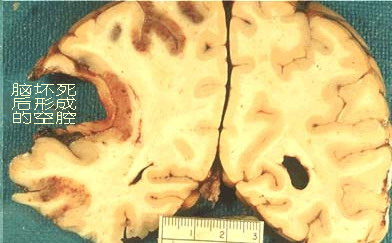

奇妙的人体奥秘无穷,有的已经为人所探知,大量的还等待我们去揭秘。就拿“再生”来说,人体有的部位具有强大的再生能力,比如骨头断了,只要对位正确,可以再生得连痕迹都看不出来。但是,人体有些部位就不同了,几乎没有再生能力,或者即使再生了,也不可能具有原本的功能,比如牙齿断了就长不出来了,脑子坏死了,只能变成“水”,不会再长出脑子的(图1)。因为人类至今没有办法让死亡的神经细胞再活起来。同理,脊髓断了后出现了“截瘫”,也就永远站不起来了,因为神经细胞死亡了。

图1 人脑出血后留下的空腔